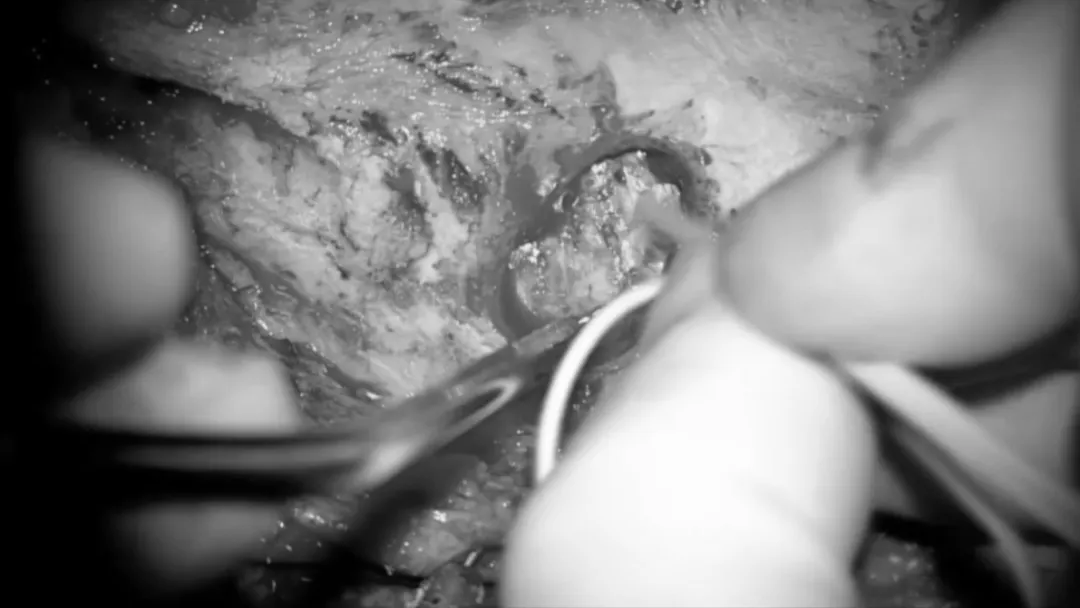

从肿瘤中分离、游离颅神经。使用显微镊来保留神经血管结构周围的蛛网膜平面。滑车神经在幕状韧带下方可见,使用CUSA刀进行逐步轻柔的肿瘤减压,这个操作对于保护位于这一重要区域的基底动脉穿支是非常重要的。

从病变中游离动脉穿支,在识别基底动脉后,使用低负压吸引器和显微剪逐渐移动肿瘤,将肿瘤从这些血管中分离揭牌。这种精细的操作是在高倍放大的显微镜下进行的,以便安全地分离蛛网膜和切断肿瘤的基底动脉及其穿支。

肿瘤的背侧表面也使用相同的技术进行解剖、分离。在脑干水肿和肿瘤紧密粘连于脑干的情况下,部分肿瘤残端需考虑保留,以避免损伤这些穿支。

第三对颅神经的识别。逐渐地,动眼神经被识别并从肿瘤中分离,同时沿着Dorello’s管方向分离解剖及保护外展神经。